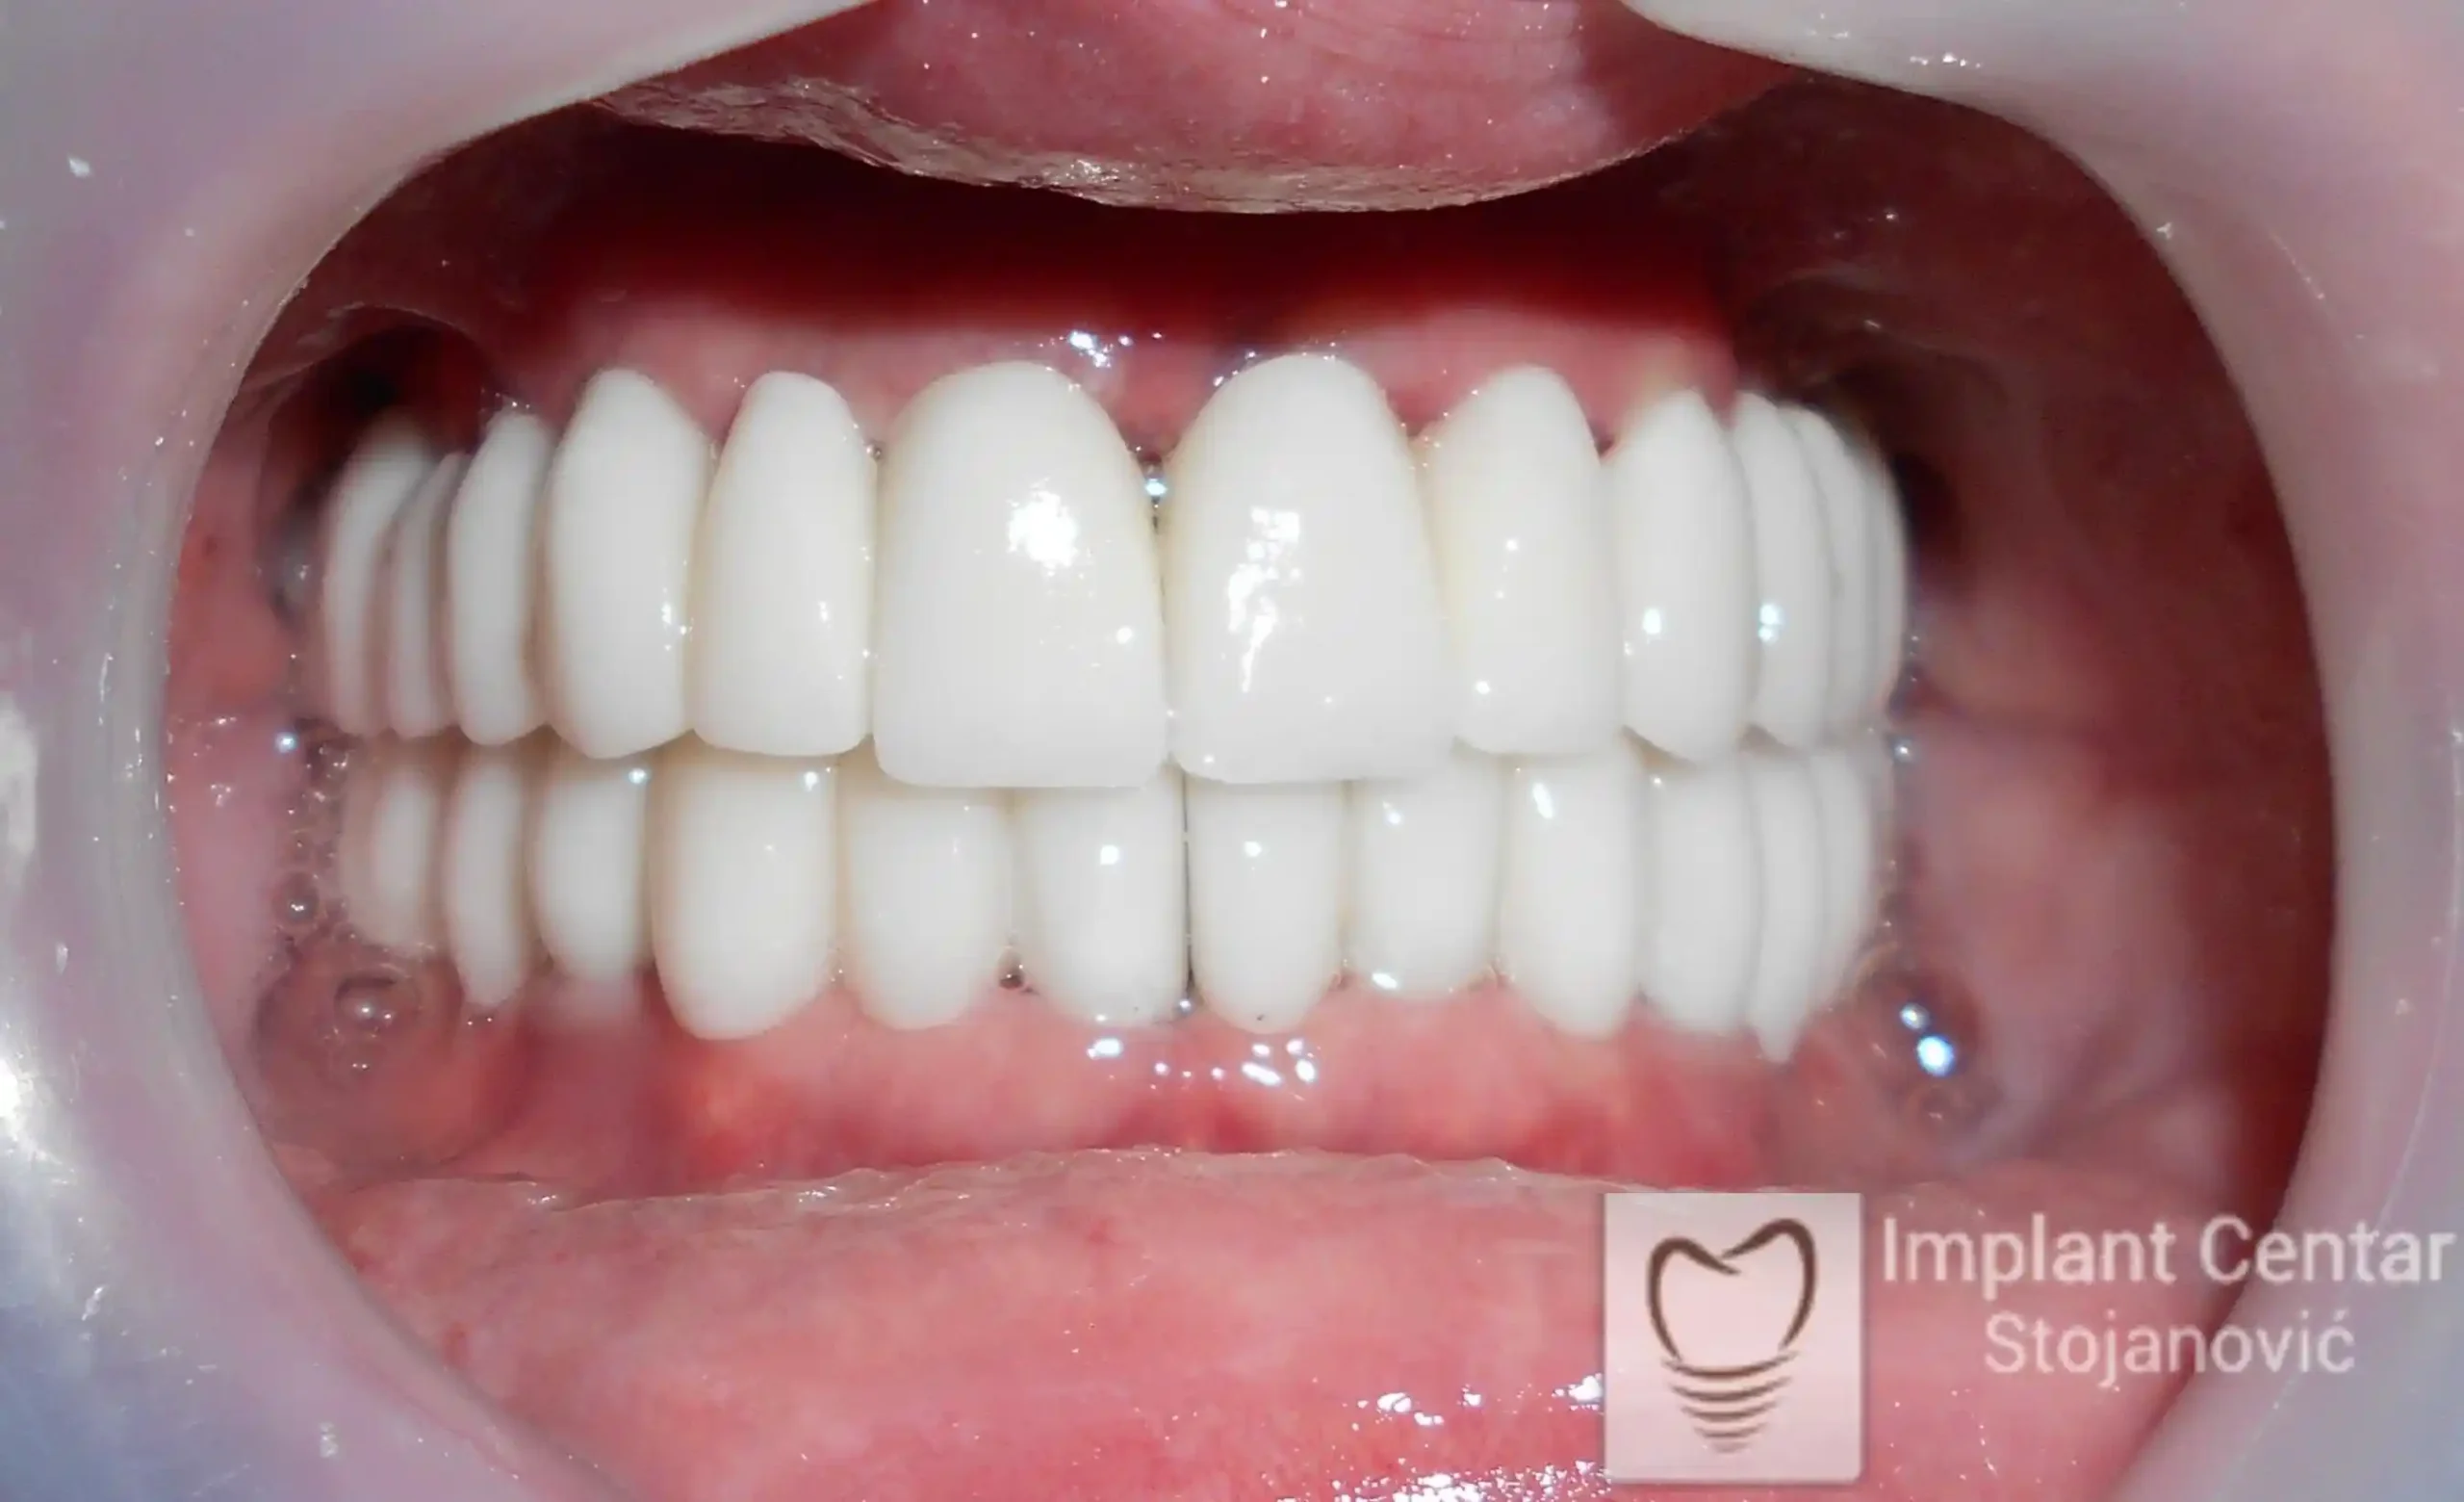

Pacijent sa rascepom usne, nepca i alveolarnog grebena uspešno je rehabilitovan fiksnim protetskim radom na implantatima. Pre dolaska u našu ordinaciju, pacijent je u gornjoj vilici nosio totalnu protezu preko preostalih zuba, dok je u donjoj vilici bio zbrinut parcijalnom mobilnom protezom. Tokom višegodišnje potrage za adekvatnim rešenjem, pacijent nije uspeo da pronađe zadovoljavajuću terapijsku opciju ni u zemlji ni u inostranstvu.

Nakon detaljnog kliničkog pregleda i analize radioloških snimaka, izrađen je sveobuhvatan plan terapije sa ciljem uklanjanja mobilnih proteza i postizanja maksimalne funkcionalne i estetske rehabilitacije. Zbog loše biološke vrednosti preostalih zuba, doneta je odluka o njihovom vađenju i ugradnji dentalnih implantata.

Poseban terapijski izazov predstavljalo je premošćavanje defekta nastalog usled rascepa, kao i ograničena količina raspoložive kosti u gornjoj vilici. Primenom većeg broja implantata i odgovarajućih procedura nadoknade kosti, postignuta je stabilna osnova za fiksni protetski rad.

Tokom perioda oseointegracije, pacijent je bio zbrinut fiksnim privremenim krunicama, čime je već pet dana nakon intervencije obezbeđena potpuna funkcionalna i estetska rehabilitacija. Nakon završetka perioda integracije implantata, izrađeni su definitivni cirkonijum-keramički mostovi na implantatima.

Pacijent je izuzetno zadovoljan postignutim rezultatom, navodeći da po prvi put jasno oseća svoje nepce tokom žvakanja, kao i da se smeje sa punim samopouzdanjem.